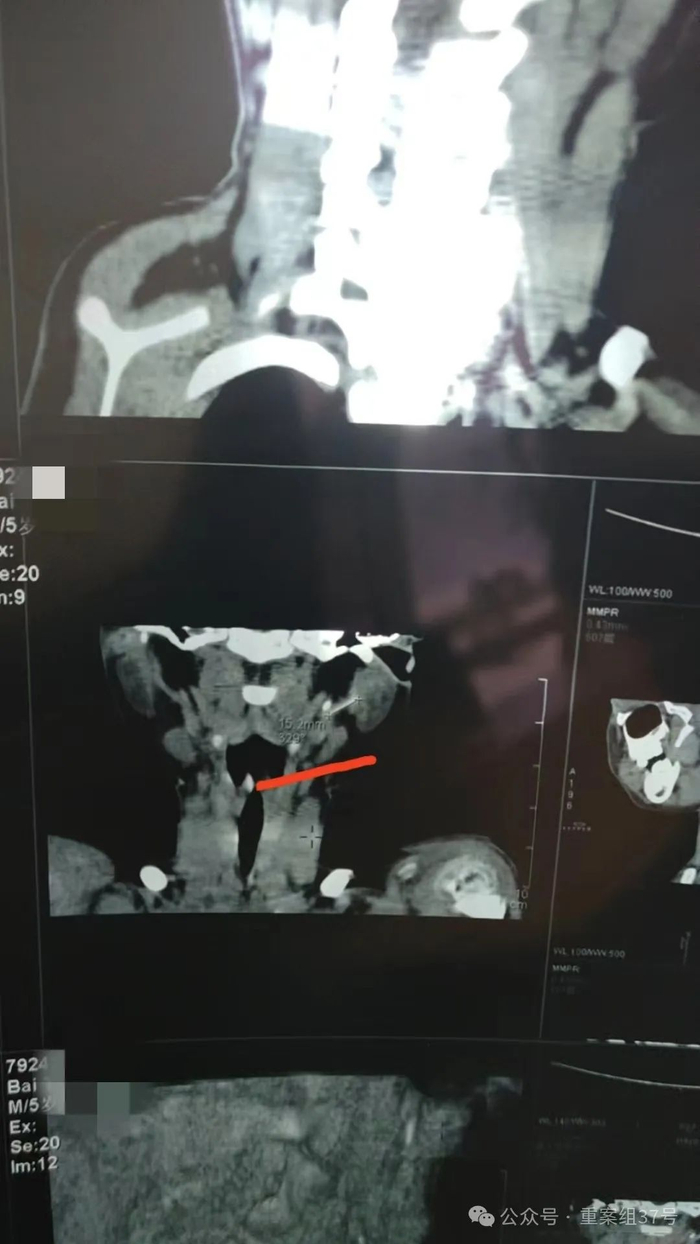

B超结果证实了这一猜测——一截长约15毫米、直径约0.8毫米的细管状影像,在小白左耳上方皮下1.3毫米处被发现,长度、形状均与留置针缺损的那截导管相符。

主刀医生宣布血管异物取出手术失败,缝合了伤口。他们推测,导管已在血管内漂移,可能到达了心脏或肺部,手术后,拍摄心脏B超及肺部CT,却没有发现导管。医生认为,导管很可能还在小白体内血管中漂移,建议动态复查。

西安交通大学第一附属医院血管外科主任医师刘建林从业近40年,从病人的血管中取出过深静脉置管的导丝、造影导管、钢质针头和留置针导管,他评价,留置针导管是最难取的。“异物越短、越细小、越不显眼,取出难度就越高。金属材质容易通过医学影像定位,但是塑料材质的留置针导管不透X射线,有一定几率会出现导管找不到的情况。”

据公众号“医学界”报道,留置针套管作为医用耗材,应遵循行业标准。中华人民共和国医药行业标准《一次性使用静脉留置针》(YY 1282—2016)规定,留置针导管要具备射线可探测性。《国际生物医学工程杂志》2021年的文章指出,多数留置针导管都设置硫酸钡显影条,能在X射线下显影。但或源于品牌差异,使用不同的显影条,在X射线下的可探测性有所不同,也不排除一些医用耗材未采用显影条。